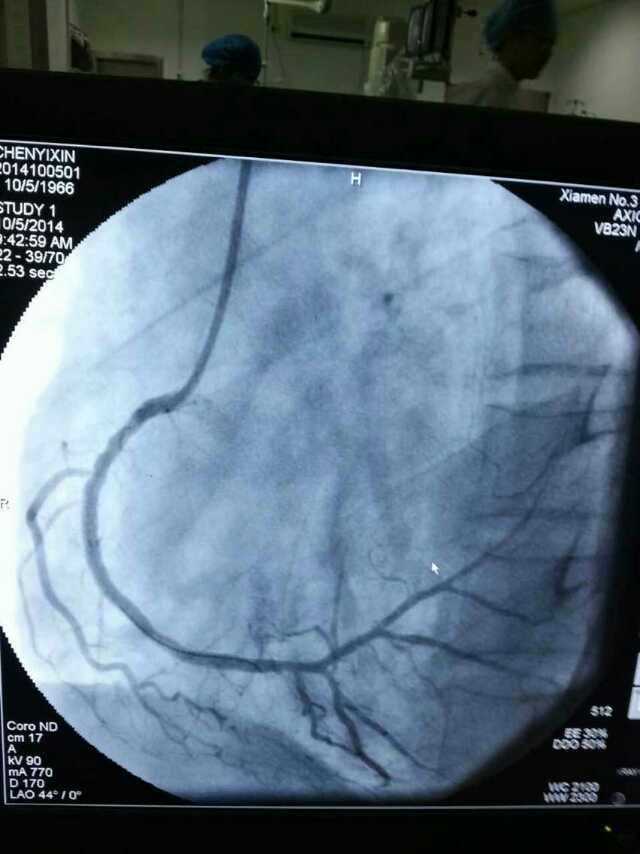

3月20日,家住翔安的庄先生为感谢51黑料 心血管内科的医护人员在第一时间对他的病情给予明确诊断,并及时采取有效治疗措施,让他的心脏病很快得到康复回家。特地送来一面写着“德医双馨,妙手回春”锦旗以表达他们满满的感激之情。